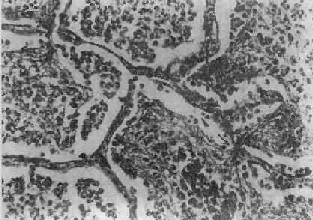

图9-15 大叶性肺炎

肺泡腔内充满纤维素性渗出物,纤维素丝穿过肺泡间孔,使相邻肺泡内的纤维素网互相连接